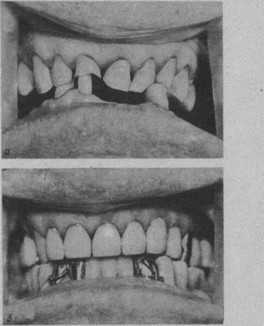

Показанием к повышению межальвеолярной высоты при устранении окклюзионных нарушений, вызванных деформациями зубных рядов, являются неглубокие деформации с понижением межальвеолярного расстояния и уменьшенной высотой нижней трети лица. В большинстве случаев это больные с генерализованной или локализованной патологической стйраемостью различной этиологии. Изменение межальвеолярного расстояния в подобных клинических условиях устраняет окклюзионные нарушения, позволяет провести рациональное протезирование, улучшает внешний вид больного и помогает предупредить или устранить дисфункцию сустава (рис. 23).

Рис. 23. Устранение нарушений окклюзии при деформации зубных рядов с патологической стираемостью с понижением межальвеолярной высоты и нижней трети лица.

Окклюзионная поверхность на верхней челюсти выровнена литыми комбинированными коронками, 3 213 покрыты коронками. Больной протезирован съемным протезом. а — до протезирования. Видна деформация окклюзионной поверхности зубных рядов. Пародонт зубов,’ удерживающих межальвеолярную высоту, испытывает большую функциональную перегрузку, о чем свидетельствуют их патологическая подвижность и атрофия пародонта; б—’после протезирования с повышением, межальвеолярной высоты.